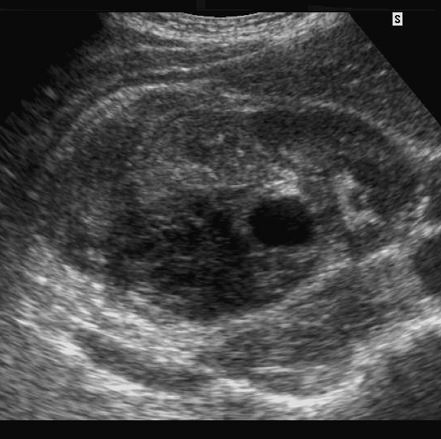

Tubular Ectasia of the Rete Testes

• The rete testes are a complex collection of small tubules that are located in the mediastinum of the testis. Fluid from the seminiferous tubules drains into the rete testis and then exits the rete testis via the efferent ductules. The efferent ductules then converge into the head of the

epididymis.

• Tubular ectasia of the rete testes is believed to be caused by some degree of outflow obstruction of the seminiferous fluid. Perhaps this is the reason why it is frequently associated with testicular cysts and spermatoceles of the epididymal head. It is also more commonly seen in patients with a history of inguinal surgery, such as hernia repairs and vasectomies.

• The key to making the diagnosis and distinguishing tubular ectasia of the rete testes from cystic testicular tumors is to note the bilateral involvement when present and to recognize the elongated shape on long-axis views of the testis.